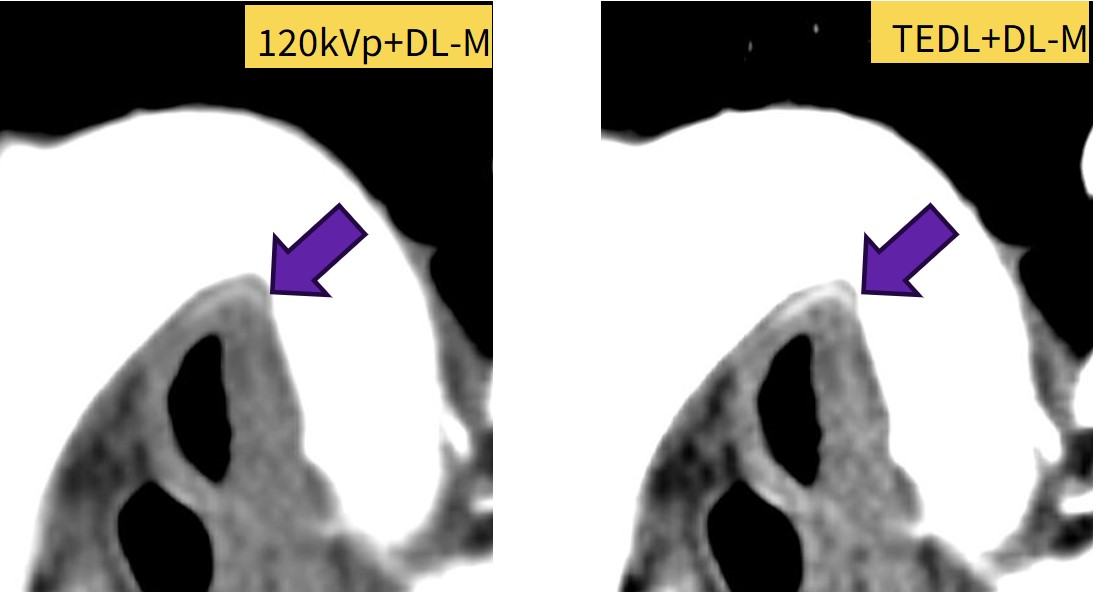

食道がんの手術では気管支動脈を温存することで術後肺炎などのリスクを低下させるため、術前に気管支動脈の走行を把握しておくことが必須となり、描出依頼がありました。

120kVpではやや分かりにくいですがTEDLでははっきりと気管支動脈が描出できた症例です。

Fig5. 描出困難な気管支動脈の視認性向上に役立った症例